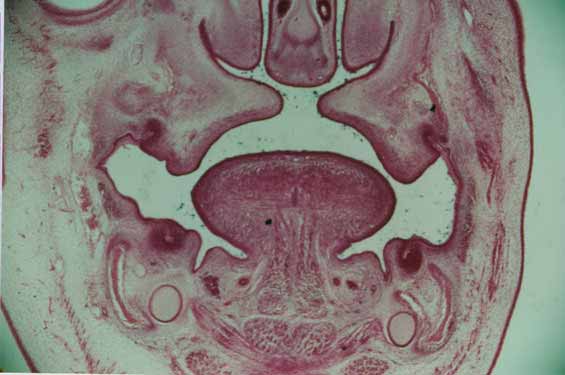

На ранних этапах развития лицевой части черепа нос и ротовая полость образуют единый стомодеум. Развитие нёба приводит к разделению стомодеума на две отдельных полости: носовую и ротовую. В краниальной части стомодеума появляется первичный небный отросток, дающий начало резцовой кости и парным вторичным небным отросткам, которые в конечном итоге формируют твердое небо. Вторичные небные отростки вначале растут вертикально вниз, к языку, затем поднимаются и растут горизонтально, чтобы соединиться по средней линии. Эпителиальный слой краев небных отростков (эпителиальная стена Hochstetter) подвергается дегенерации путем апоптоза, а подлежащая соединительная ткань соединяется, образуя твердое нёбо (рис. 11).

Рис.11. Сращение небных отростков по средней линии. Hochstetler's эпителиальная стенка все еще присутствует по средней линии.

Недостаточное слияние небных отростков приводит к появлению небной расщелины с соединением между ротовой полостью и полостью носа (Рис.12). Это ведет к расстройствам питания.

Рис.12. Не сращенные небные отростки с небной расщелиной и соединением между ротовой полостью и полостью носа.